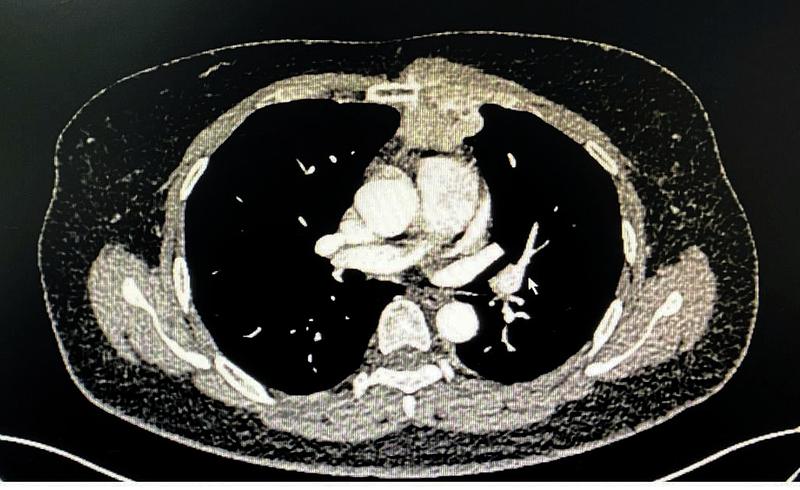

病例2:术前胸部增强CT

另一位女性患者发现左前胸壁肿物1周就诊,胸部CT示胸壁及前纵隔可见不规则软组织密度影,大小约48mmx40mm,长径约10cm,病灶与临近胸骨及左侧第2、3肋软骨分界不清。行超声引导下肿物穿刺活检,病理显示间叶来源肿瘤。肿瘤突破纵隔,侵犯了部分胸骨、左侧肋软骨以及胸部肌肉组织,此类型病例较少见,需切除部分受损胸骨及肋软骨,并对缺损的胸壁进行重建。由于缺损处较大,合适胸肋骨重建材料(如相应钢板和3D打印材料)价格昂贵,病人经济状况不能承担,李少民主任利用现有的胸骨钢板、肋骨环抱器以及经李少民主任改良的勾状的肋骨环抱器进行拼接,解决了长度的问题,稳定性上也表现出色,完美地重建了胸廓的完整性。手术入路也开创性的选择了胸腔镜和传统开胸手术结合的方式,从剑突下进行微创手术游离肿瘤的两侧及基底部,再从左侧胸壁开口,完整切除胸壁受侵组织,然后像打开“盖子”一样,移除肿瘤,避免了正中劈开胸骨的巨大创伤。手术过程顺利,术后恢复良好。